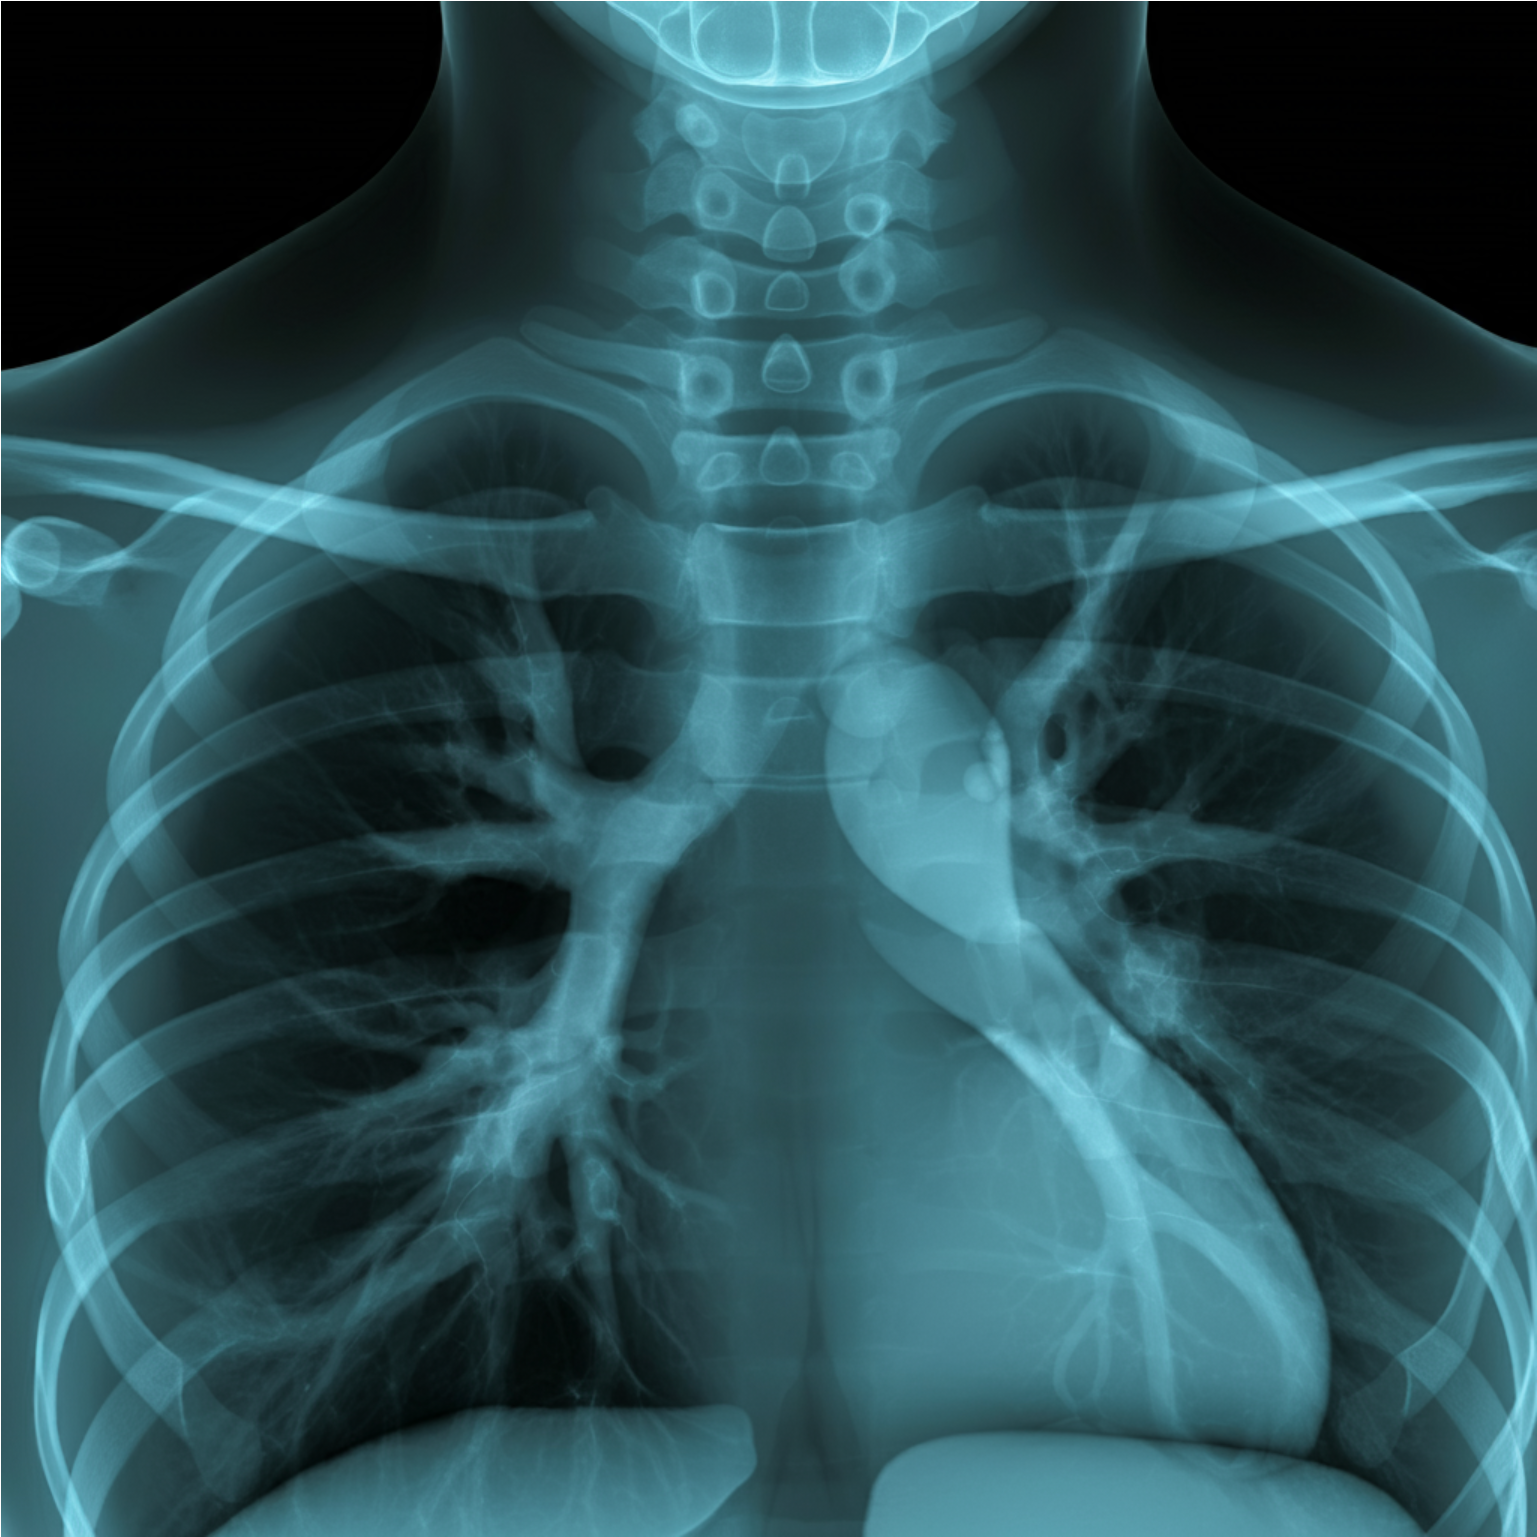

2. 호흡기계

- 호흡수를 최대 10% 증가시키고, 기관지를 수축시켜 호흡곤란을 유발합니다.

- 만성 폐쇄성 폐 질환 (COPD) 위험을 최대 4배 증가시킵니다.